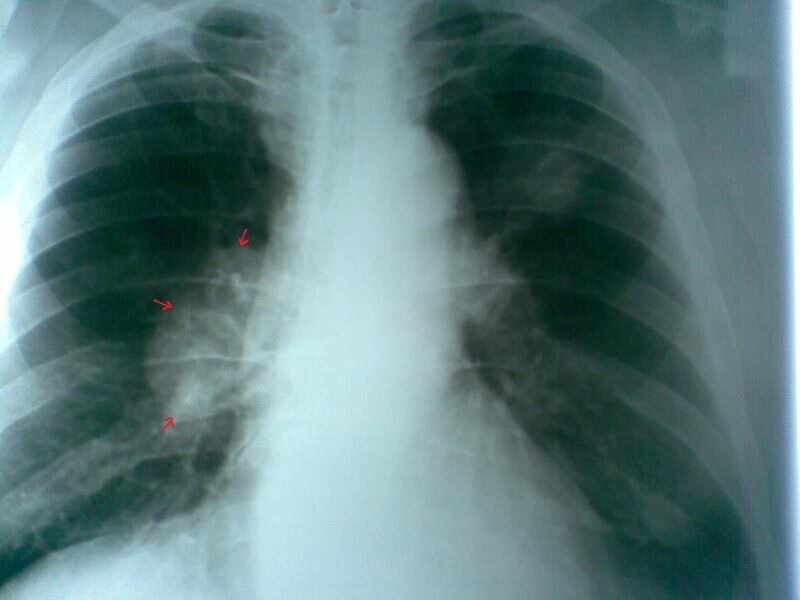

Существует ошибочное мнение, что невозможно увидеть рак легких на флюорографии. Флюорография позволяет выявить патологические процессы, происходящие в легких. Опытный специалист всегда обращает внимание на изображение, на котором наблюдается затемнение либо уплотнение.

В то же время быстро и легко выявить онкологию легких с помощью флюорографии удается не всегда. Поставить диагноз получается при достижении карциномой внушительных размеров и в том случае, если на снимке хорошо видно новообразование. Обычно это происходит при достижении опухоли легких последней стадии либо при нахождении человека в тяжелом состоянии, которое сопровождается развитием множества осложнений. При незначительном затемнении на флюорографическом снимке для подтверждения диагноза назначаются дополнительные исследования.

Флюорография может не показать злокачественное новообразование в легких и в том случае, если оно локализуется на поверхности, а не в глубине. При таком патологическом состоянии органа специалист назначает пациенту проведение рентгена, компьютерной либо магнитно-резонансной томографии, показывающие, как выглядит проблемная зона.

Такой метод исследования, как флюорография, может показать в легких, скопление в них жидкости и наличие очагов инфекционных поражений. Кроме этого, такой метод диагностики позволяет рассмотреть корни бронхов и легких, которые при различных патологиях могут быть уплотнены либо расширены.